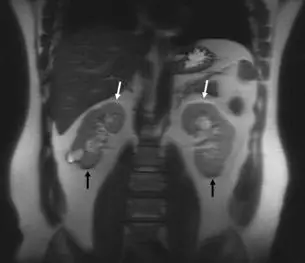

影像為雙腎冠狀切面 MRI(Coronal view)。白色箭號(↓)指向雙側腎臟的上緣,可見明顯的亮帶(高訊號帶);黑色箭號(↑)指向雙側腎臟的下緣,可見明顯的暗帶(低訊號帶)。這種在器官邊界一側出現亮帶、另一側出現暗帶的對稱性表現,是化學位移第一類偽影的經典影像特徵。腎臟為含水組織,周圍被腎周脂肪(perirenal fat)包圍,脂-水交界面因頻率差異而產生像素空間錯位,形成本圖所見的黑白邊框現象。

(A) 化學位移(chemical shift) — 正確答案。脂肪與水中的氫質子因化學環境不同,共振頻率相差約 3.4 ppm(1.5T 下約 215 Hz、3.0T 下約 430 Hz)。空間定位使用頻率編碼梯度時,系統誤以為脂肪質子的訊號來自頻率對應的另一個位置,導致脂-水交界面兩側分別出現訊號疊加(亮帶)與訊號缺失(暗帶)。本圖雙腎上緣亮帶、下緣暗帶即為此偽影的典型表現